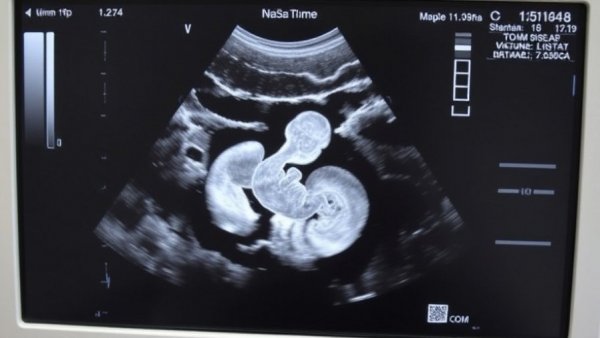

In a significant leap for maternal healthcare, BioticsAI has gained FDA approval for its innovative AI-powered fetal ultrasound technology. This breakthrough, awarded at the TechCrunch Disrupt Battlefield 2023, positions BioticsAI at the forefront of addressing critical challenges in prenatal diagnostics. Founder and CEO Robhy Bustami, whose background in obstetrics informs his approach, underscored the importance of enhanced ultrasound image quality to mitigate misdiagnosis rates—a concerning issue in the U.S., which reports alarming maternal mortality rates, particularly among Black women.

Ultrasound imaging has long been a mainstay in monitoring pregnancies; however, the quality of these images often results in misinterpretation and potential health risks for mothers and their babies. Bustami's solution uses advanced computer vision AI to assess the quality of fetal ultrasounds, ensuring a deeper, clearer understanding of prenatal health. This technology empowers clinicians by automating reporting and providing comprehensive analytics, merging seamlessly into the existing clinical workflows, which is paramount in an ever-evolving healthcare landscape.